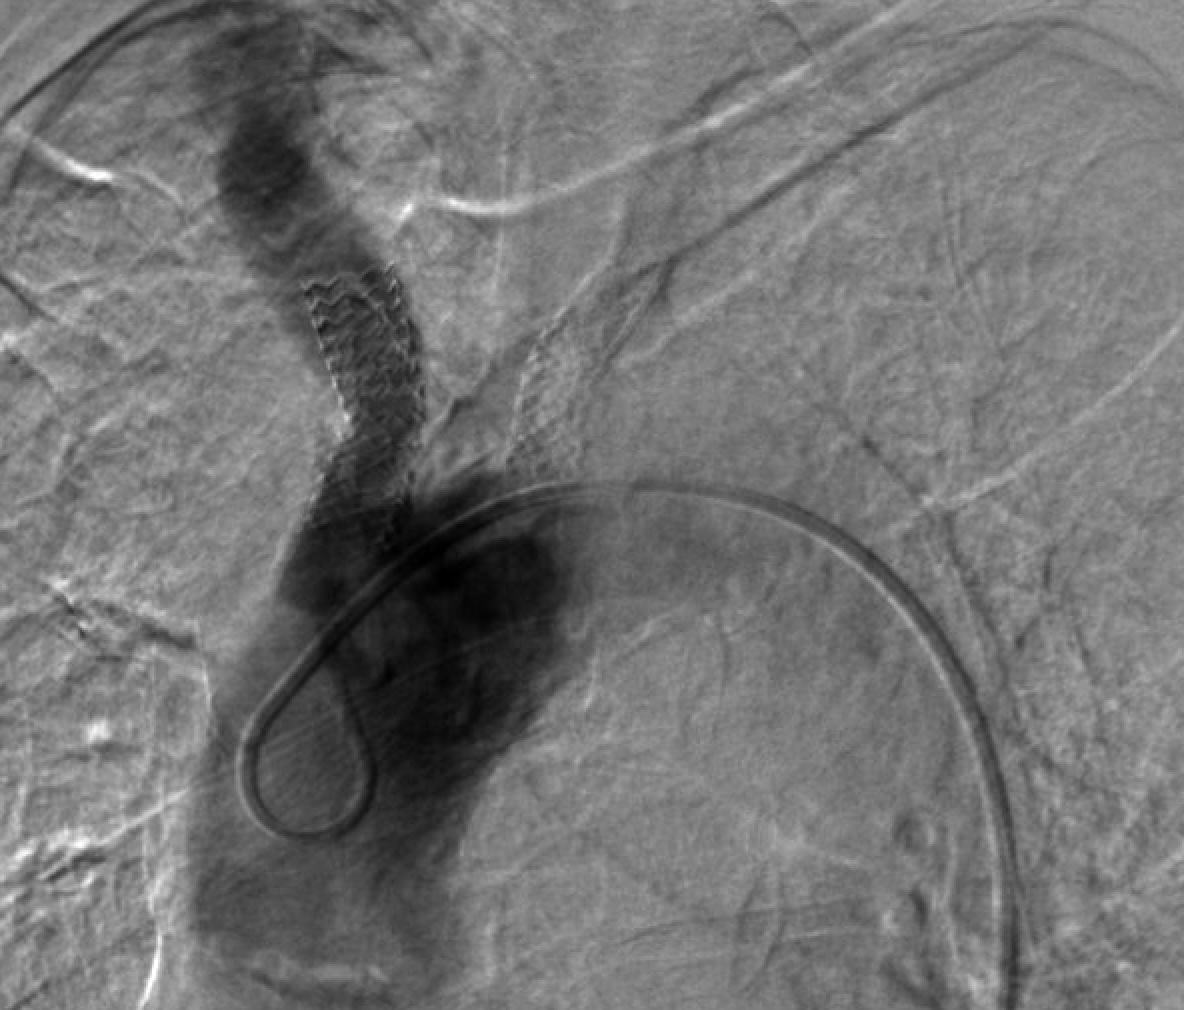

Considering the patient's comorbidities, an endovascular approach was the safest approach. Dual access was achieved using a 6F sheath in the right radial artery and another 6F sheath in the right femoral artery; an aortogram was then conducted showing severe stenosis in the right innominate artery (Figure 1). A carotid angiogram was performed, revealing a vessel size measuring 6 to 7 mm. We advanced a BareWire guidewire (Abbott Cardiovascular) and proceeded with the successful deployment of an Emboshield NAV6 filter (Abbott Cardiovascular) in the right ICA through the radial access as it was the only route for delivering it to prevent entrapment of the filter if placed from the femoral route (Figure 2).

At this moment we elected to proceed with endovascular intervention through the radial access. Via right radial access, a long Runthrough wire (Terumo Interventional Systems) crossed the stenosis into the distal aorta, and we upgraded the sheath to 7F over both wires (BareWire and long Runthrough). We exchanged the long Runthrough wire with a Glidewire Advantage (Terumo Interventional Systems) via a TrailBlazer support catheter (Medtronic). We predilated with an 8-mm balloon and then an 8-mm x 29-mm Omnilink ballon-expandable stent (Abbott Cardiovascular) was successfully placed in the right innominate artery and deployed (Figure 3). Next, a pigtail catheter was advanced through the groin and angiography was performed, showing an under-expanded and malapposed mid to distal area of the stent (Figure 4), which was post-dilated with a 14-mm x 10-mm Armada balloon (Abbott Cardiovascular) (Figure 5), after which the filter was removed and a final aortogram showed good results with better apposition without complications (Figure 6).

During a follow-up appointment 1 month later, the patient reported no dizziness, fainting, or near-fainting episodes, TIA, or stroke-like symptoms. Her right arm heaviness and numbness were resolved completely and she had a strong radial pulse bilaterally. A carotid and subclavian Doppler examination was scheduled for 6 months post-procedure to assess the condition of the stent. This showed multiphasic waveforms in both subclavian arteries with mild disease in the right carotid artery and the previous left subclavian stent without any elevated velocities or evidence of stenosis in the right innominate or subclavian arteries. (Figure 7).